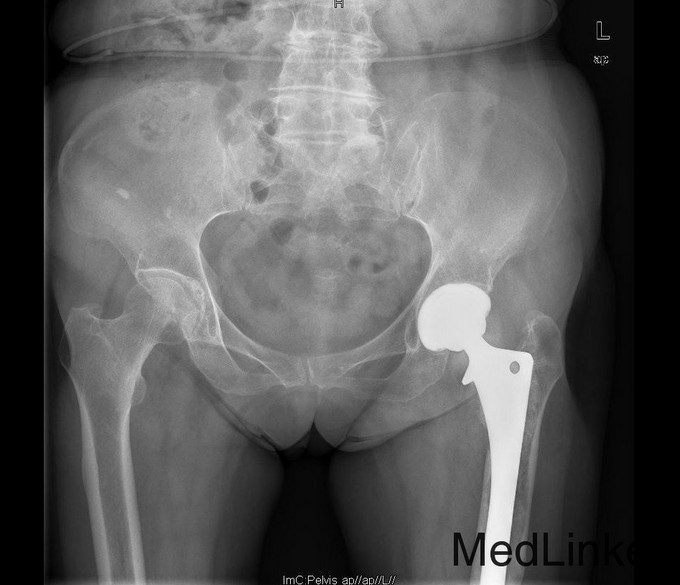

查体:专科:左髋部后外侧陈旧手术瘢痕,左髋关节前方压痛、无轴向叩击痛阴性,无大转子叩击痛,双下肢感觉及血运均正常。双下肢肌力V级。动量:右髋内外旋诱发疼痛,屈曲90度疼痛。外旋明显滚动试验阴性,左髋4字试验阳性。双下肢等长。左髋关节屈90°,伸0°,外展40°,内收20°,内旋30°外旋10°。右髋关节屈120°,伸直0°,外展40°,内收20°,内旋30°外旋30°。 辅助检查:2010-12-08 ESR 6.0mm/h,2011-01-04外院CRP8.5mg/l(参考范围0-10mg/l)X线示左双动股骨头置换术后,假体松动、下沉,髓腔内可见骨水泥影。近端干骺端骨质明显缺损。髓腔内侧皮质形态不规则。

诊断:左双动股骨头置换术后假体松动、下沉、股骨骨缺损(PaproskyII型) 治疗:患者在全麻下左双动股骨头假体取出+同种异体骨植骨+左全髋关节翻修术,术后予以抗炎(二联)+抗凝+镇痛+护胃+补液等治疗,并予以抗骨质疏松药物